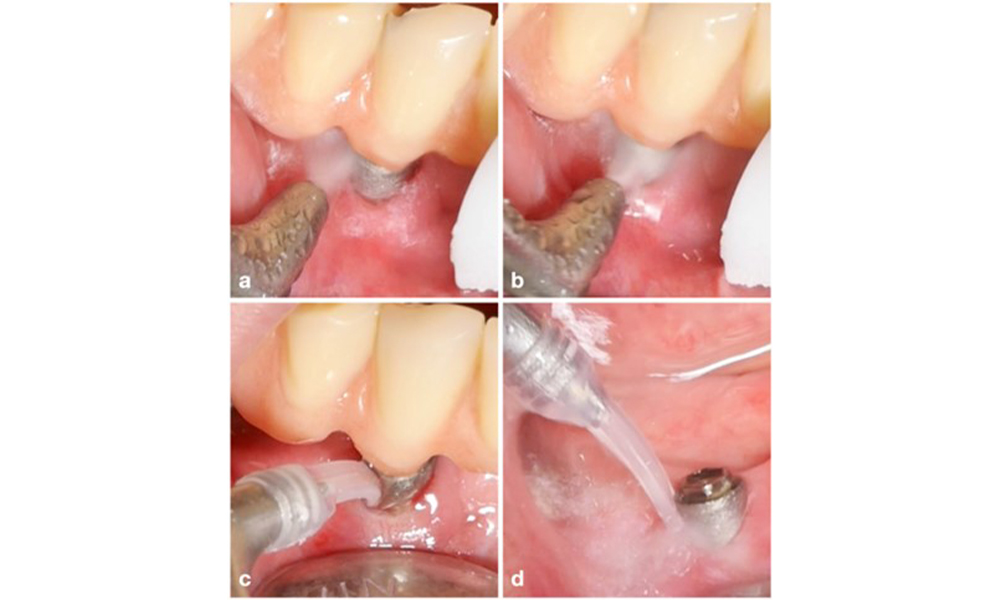

Изборът на средство зависи от клиничните обстоятелства, като например разликата между зъбен камък и мека плака. По този начин, в случаите със зъбен камък първо трябва да се използват титаниеви или пластмасови кюрети или специални накрайници за ултразвукови скалери, последвани от използването на устройство за въздушно полиране (фигура 7). В случаите само с натрупване на мека плака може да е достатъчно само въздушно полиране. Устройствата за въздушно полиране са лесни за ползвателя и пациента и са поне толкова ефективни, колкото стандартните инструменти (Schwarz et al. 2015a).

Лечението на периимплантит при импланти, оценени като лечими, се състои от нехирургична фаза, която често е последвана от хирургична интервенция. Нехирургичните процедури са подобни на тези, прилагани за лечение на периимплантатен мукозит. Лабораторните експерименти показват, че устройствата за въздушно полиране със субгингивални накрайници изглежда осигуряват определени предимства по отношение на отстраняването на биофилм в сравнение с ръчните или ултразвукови инструменти (Herrera et al. 2023; Moharrami et al. 2019; Ronay et al. 2017) ( фигура 9).

Реконструктивна процедура се препоръчва за импланти с модифицирани повърхности и вътрекостни дефекти, където потенциалът за ре-остеоинтеграция е много по-висок (Monje et al. 2023; Renvert et al. 2009). Това може да включва използването на автогенна кост, костозаместващи материали и/или мембрани (фигура 13) (Donos et al. 2023). Разбира се, реконструктивният подход налага цялостно обеззаразяване на повърхността на импланта. Както лабораторните, така и предклиничните проучвания показват, че пълното отстраняване на биофилма от повърхността на импланта не е възможно (Subramani & Wismeijer 2012). Поради това се препоръчва да се използва комбинация от механични и химични мерки за ефективно обеззаразяване, въпреки че нито един специфичен метод не може да се счита за по-добър (Ramanauskaite et al. 2023; Wilensky et al. 2023). Според няколко лабораторни проучвания устройствата за въздушно полиране са показали по-висока ефективност при отстраняване на биофилм (Francis et al. 2022; Keim et al. 2019, Sahrmann et al., 2015). Въпреки това е важно да се отбележи, че интраоперативната употреба на въздушно полиране не е по предназначение.